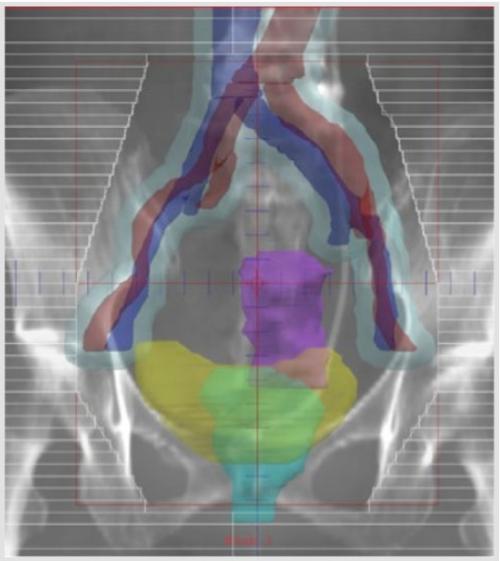

外部照射の治療範囲は、子宮の病巣から腫瘍が拡がる可能性のある腟、子宮傍結合織、骨盤リンパ節までを含めます。図aは、リンパ管造影の写真に照射野を重ねたものです。骨盤リンパ節(内・外・総腸骨・閉鎖節・仙骨前リンパ節)は照射野に含まれます。図bはCT上で再構成した、実際の照射範囲の一例です。

図b